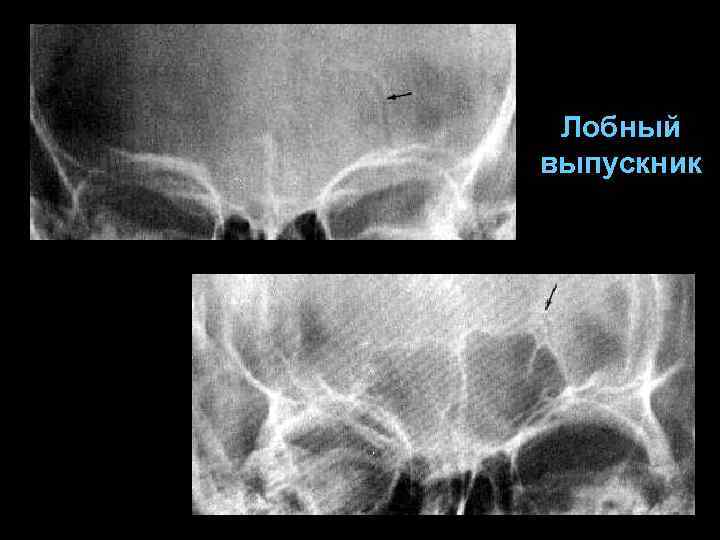

Каналы эмиссарных вен (выпускников) § § Четко очерченные лентовидные участки просветления с уплотненными стенками особенность – строгое анатомическое расположение

Канал лобной эмиссарной вены идет от верхнего сагиттального синуса и заканчивается отверстием в области надглазничного края (30 -70 мм)

Лобный выпускник